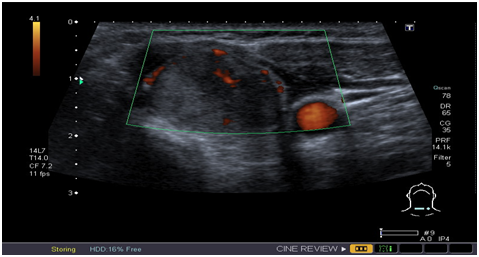

Thyroid cancers are the commonest cause of death among all the endocrine malignancies. Only 1 in 20 clinically detected thyroid nodules are malignant.2‒11 Several risk factors for malignant nodule have been identified (Table 1). Thyroid nodules under the age of 16 are highly likely to be papillary cancers. About 15 - 30% of CT PET positive nodules turn out to be malignant. Following are the US features suspicious for malignancy, which would definitely indicate FNAC: cells taller than wide in shape, cell with an irregular spiculated outline with a halo, presence of a hypoechogenicity in a solid nodule, micro calcifications and increased vascularity (Figure 1). Micro calcifications are thought to be due to superimposition of Psammoma bodies upon one another and are most suggestive of Papillary thyroid cancer and have a specificity of up to 95%.

Figure 1 US showing solid nodule with micro calcification and increased vascularity.